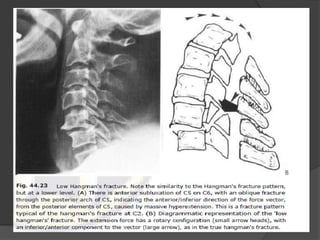

Hangman’s Fracture C-2



Fx through the pars

interarticularis of C2

secondary to

hyperextension

Best seen on lateral

view

Hyperextention injury

Stable fracture ?

Classification of Hangman' s fractures

Type I (65%)

 hair-line fracture

 C2-3 disc normal

Type II (28%)

 displaced C2

 disrupted C2-3 disc

 ligamentous rupture with

instability

 C3 anterosuperior compression

fracture

Type III (7%)

 C2-3 Bilateral interfacet dislocation

 Severe instability

HANGMAN FRACTURE

TYPE 3

Prevertebral soft

tissue swelling

Anterior

dislocation of the

C2 vertebral body

BILATRAL C2 pars

interarticularis

fractures.